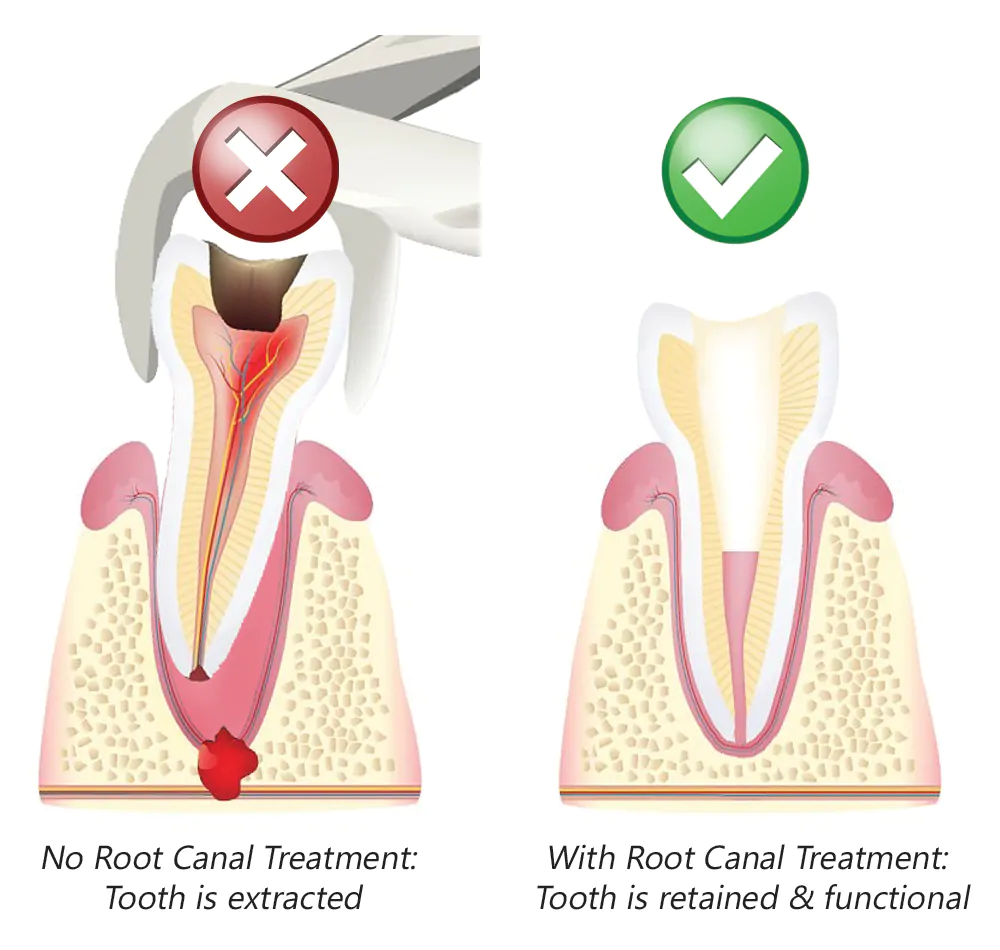

No, with modern anesthesia and advanced technology, root canal treatments are as comfortable as getting a standard filling. Our clinic specializes in utilizing painless procedures.